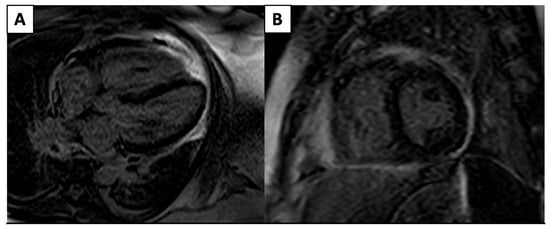

| Imaging Modality | Imaging Illustrations | Description |

|---|---|---|

| Cardiac MRI | ![]() | Short-axis view reveal interventricular mid-myocardial LGE (black arrow). |